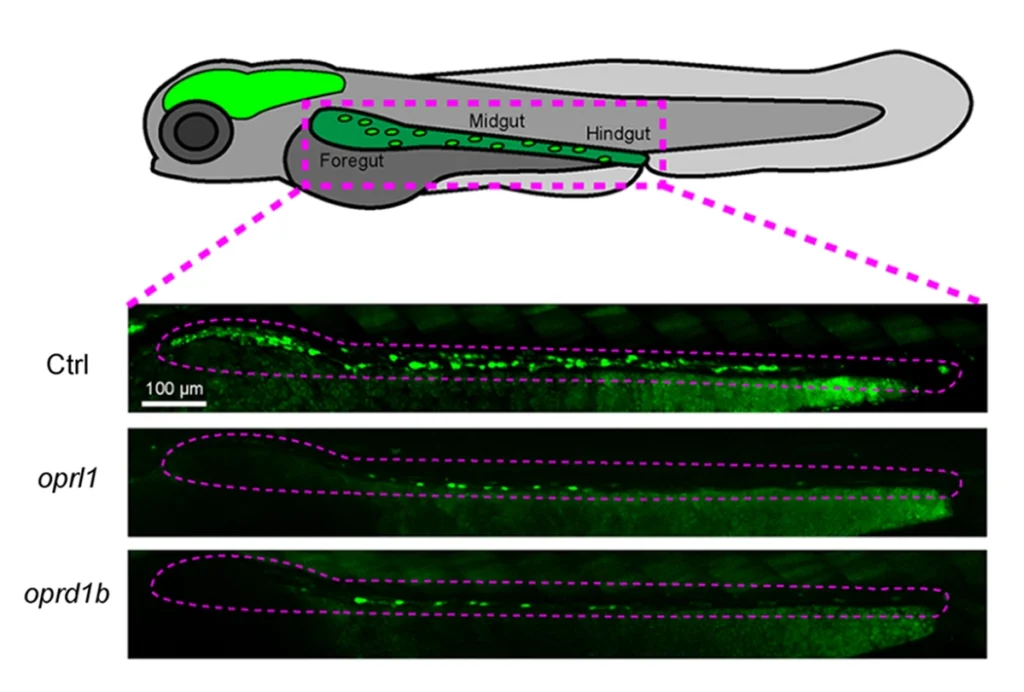

Opioid receptors may guide formation of gut nervous system in zebrafish

Fish lacking functional copies of the receptors have fewer enteric neurons than usual, but the findings await further validation.

Opioid receptors may guide formation of gut nervous system in zebrafish

Fish lacking functional copies of the receptors have fewer enteric neurons than usual, but the findings await further validation.